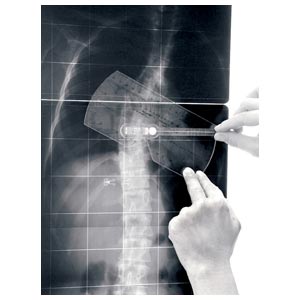

Strumento per la misurazione dell'angolo di Cobb e del gibbo. L'inclinometro è costituito da 1 elemento quasi-rettangolare di plexiglas recante una scala goniometrica, al cui centro è posizionata una piccola asta libera di ruotare e recante una bolla; l'estremità libera dell'astareca l'indice di lettura per la scala goniometrica. Il lato più lungo del rettangolo presenta una rientranza per renderne più agevole l'applicazione sul paziente (nel caso in cui le spinose siano sporgenti).

L'inclinometro è uno strumento manuale, normalmente utilizzato in due situazioni cliniche: • nella misurazione dell'angolo di rotazione del tronco durante il test di anteroflessione • nella misurazione dell'angolo di Cobb sulle radiografie (sia in proiezione AP che LL), quindi sia nella scoliosi che nella cifosi/lordosi.

Un vantaggio dell'inclinometro sugli altri strumenti è dato infine dalla possibilità di misurare sia l'angolo di rotazione del tronco (gibbo) sul paziente, sia l'angolo di Cobb sulle radiografie con un solo semplice strumento.